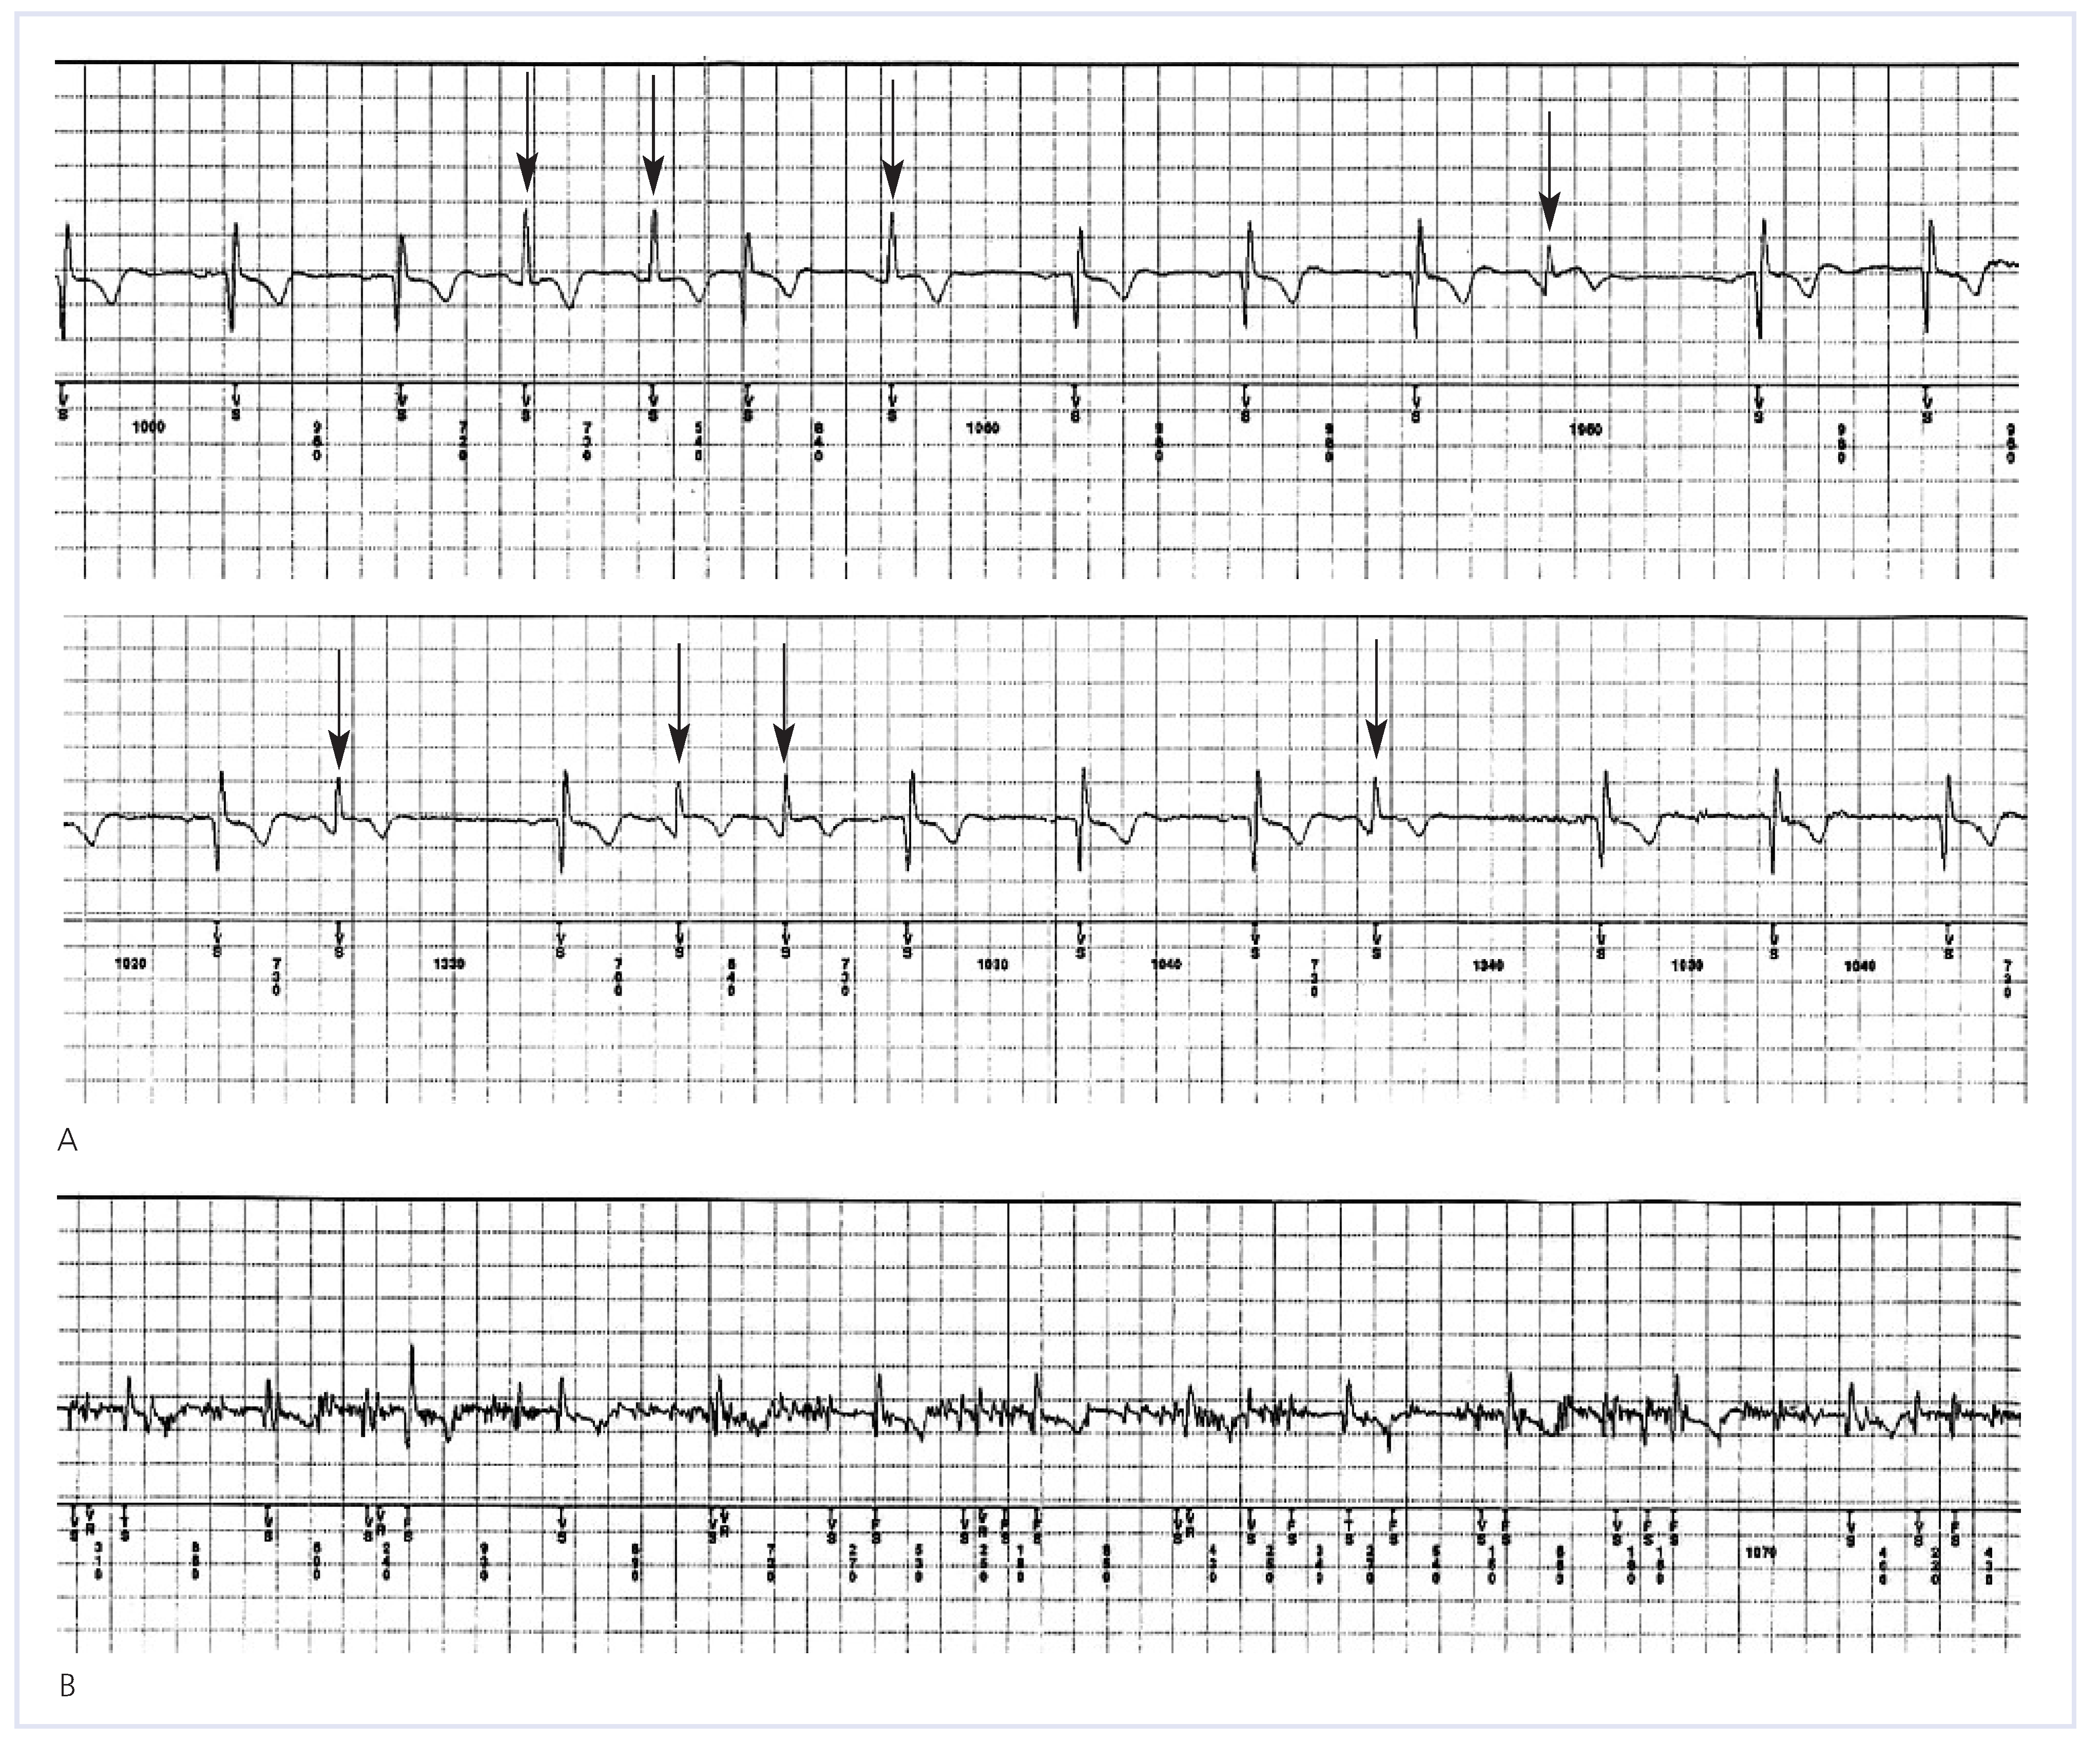

Figure 3. Inappropriate detection of AF. Shown in (A) an example of inappropriate detection of AF triggered by irregularities of R-R intervals due to frequent ventricular premature beats (arrows). (B) shows another example of inappropriate detection of AF due to high-frequency muscle noise detection. The patient was exercising at that time wearing a backpack.